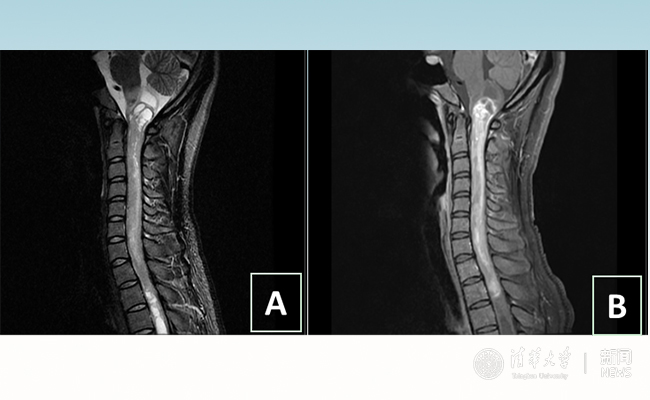

2018.01拯救“90后”女孩 清华长庚神经外科切除20多公分髓内肿瘤

“愿得韶华刹那,开得满树芳华。”27岁的患者小甜(化名)在乐动平台附属北京清华长庚医院成功进行了手术,神经外科主任王贵怀为其切除了自延髓至胸髓的长达20余公分的脊髓内肿瘤。1月9日,小甜顺利出院,再续芳华!